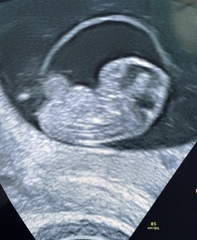

Got myself in a flap because my RHR dropped massively and my symptoms were disappearing already. But had my early scan today and everything is fine thank god 😍 measuring ahead at 8+5.